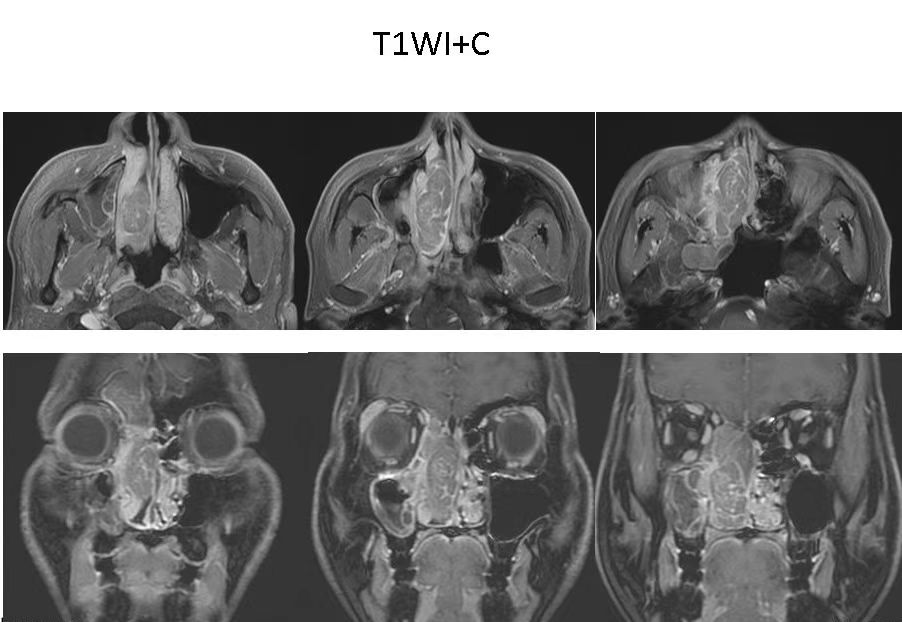

5. 增强扫描辅助,提升鉴别诊断准确性

增强MRI检查进一步提升了诊断效能。通过静脉注射造影剂,可强化病变与正常组织的信号对比,帮助医生精准判断病变血供情况,为鉴别病变性质、提高诊断准确率提供支撑。